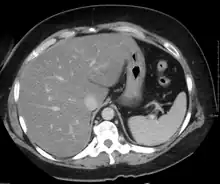

Medical imaging

On X-ray computed tomography (CT), the increased fat component will decrease the density of the liver tissue, making the image less bright. Typically the density of the spleen and liver are roughly equivalent. In steatosis, there is a difference between the density and brightness of the two organs, with the liver appearing darker.[12] On ultrasound, fat is more echogenic (capable of reflecting sound waves). The combination of liver steatosis being dark on CT and bright on ultrasound is sometimes known as the flip flop sign.